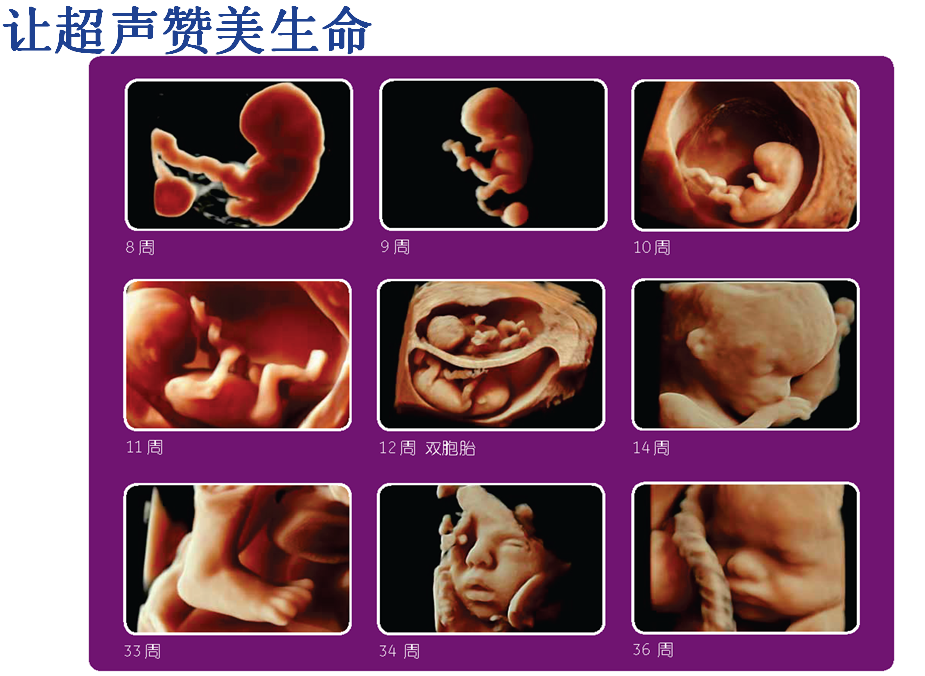

四維與三維彩超的區(qū)別:四維彩超也稱為實(shí)時三維彩超,三維彩超是靜態(tài)的,只能是某個時間點(diǎn)上的照片,四維彩超是動態(tài)的,就是在三維圖像上加上時間軸,顯示隨著時間變化而變化的立體圖像,能夠顯示未出生的寶寶的實(shí)時動態(tài)活動圖像,如打哈欠、伸懶腰、吮手指等等奇妙的動作,所以四維看起來會更清楚明晰。

2、孕11~13周彩超檢查,項(xiàng)目包括:測量胎兒頭臀徑,估算孕齡大小,測量胎兒勁項(xiàng)透明層(NT)的厚度,用于篩查胎兒染色體疾病。

3、中孕期孕22~26周,四維胎兒結(jié)構(gòu)畸形篩查檢查時間,彩超胎兒形態(tài)結(jié)構(gòu)檢查,檢查是否存在致死性嚴(yán)重畸形。